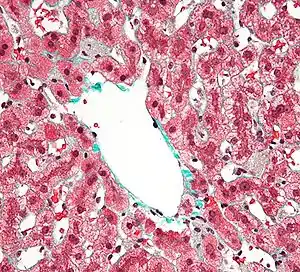

Клітини Купфера з сірою зернистою цитоплазми в ураженій печінки. Біопсія печінки. Триколірне забарвлення.